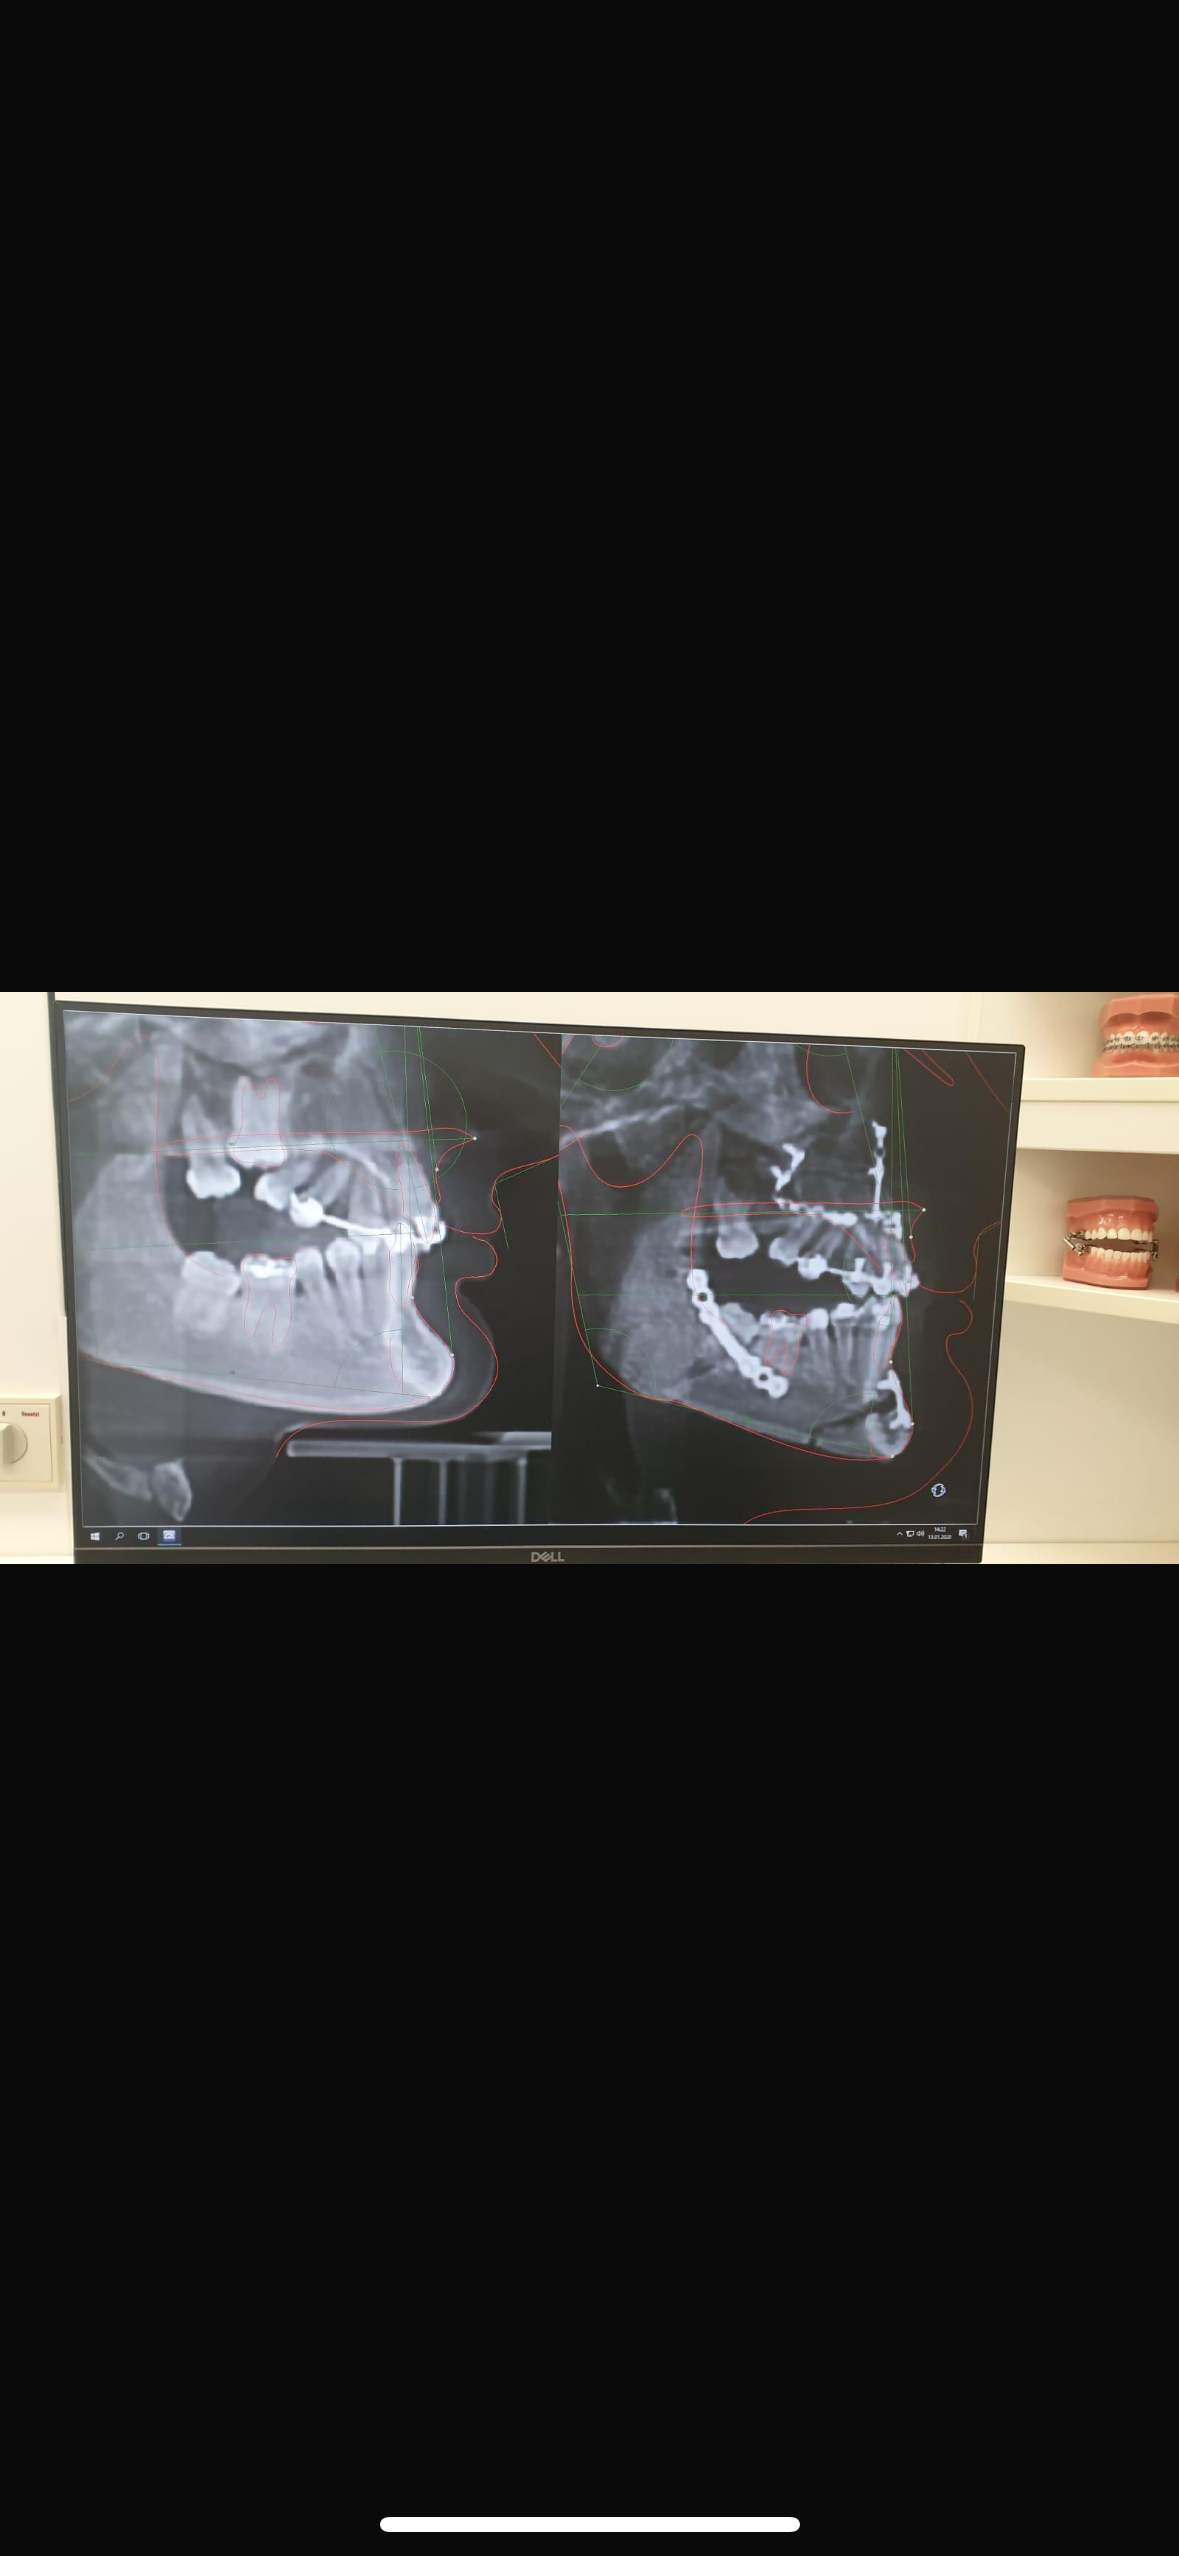

2019 große Operation komplette Kieferumstellung (Bruch des gesamten Kiefers und neu Verschraubung) mit der Annahme danach wird alles gut und ich kann endlich vernünftig kauen. Nachdem Schmerzhafte Tage und schwierige Monate der flüssigen Ernährung überstanden waren und die nächsten Termine zur Weiterbehandlung anstanden wurde klar dass das Ergebnis nicht 100%ig erreicht wurde und Fragen aufkamen wie es nun weitergeht. Anschließend bekam ich Plastikschienen über meine Zähne damit mein Kiefer sich nicht wieder zurückbildet und ich meine Muskulatur trainiere. Zum ersten Mal hinten kauen, endlich.